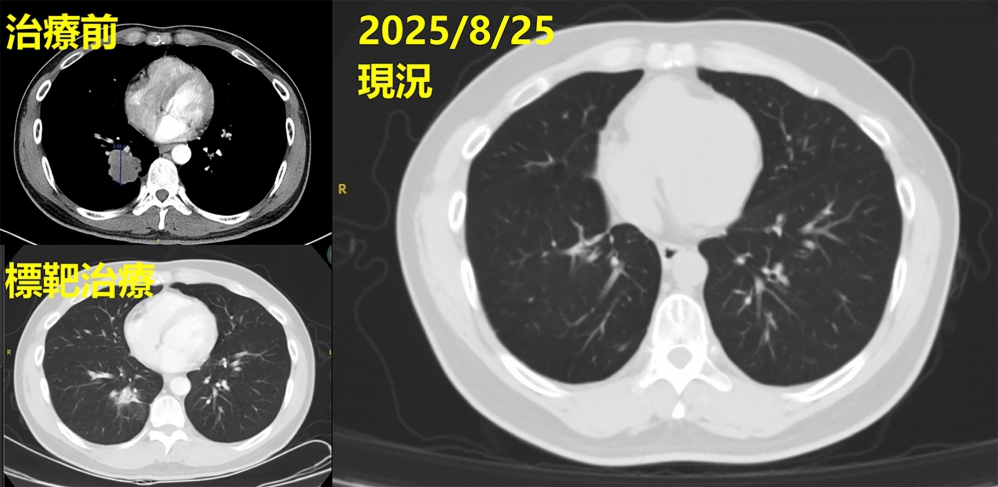

林主任說,病人入院時,醫院依臨床流程完成初步基因檢測,不能使用突變標靶,團隊持續評估治療方向,協助病人參與國衛院臨床基因試驗,最終發現具EGFR exon 19 deletion突變,可以申請第三代EGFR標靶藥物,讓治療更具針對性和精準性。

林聖皓醫師說,經一段時間影像追蹤,顯示肺部腫瘤從原本的4公分縮小為2.8公分,控制成效顯著,儘管標靶藥物初期控制良好,許姓患者仍出現神經症狀,胸腔內科隨即啟動跨科整合照護,與神經外科孫立偉醫師合作完成腦部腫瘤手術,術後雖神經功能逐漸恢復,但考量治療效果,經與胸腔外科召開跨科討論後,由洪維亨醫師進行「肺葉切除」手術,達成更徹底控制。

林主任說,在家人和團隊陪伴下,許先生跨出關鍵一步而接受治療,術後恢復良好,現已重返職場,轉為計程車司機。